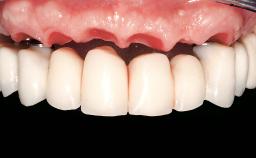

Immediate Loading of Four Implants in the Mandible and Six Implants in the Maxilla and Final Restoration with a Full-Arch Metal Framework FDP and a Full-Arch CAD/CAM Zirconia Framework FDP